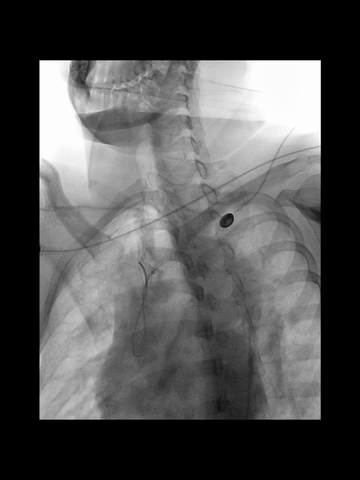

耐心冒烟下,调整导管头在无名动脉内指向左侧,同时回拉导管,进入右CCA,后上高导丝,长鞘沿5F管顺利进入右CCA,后在导管导丝导引下,长鞘头端上高到右C1远端,建立可靠的治疗通路。